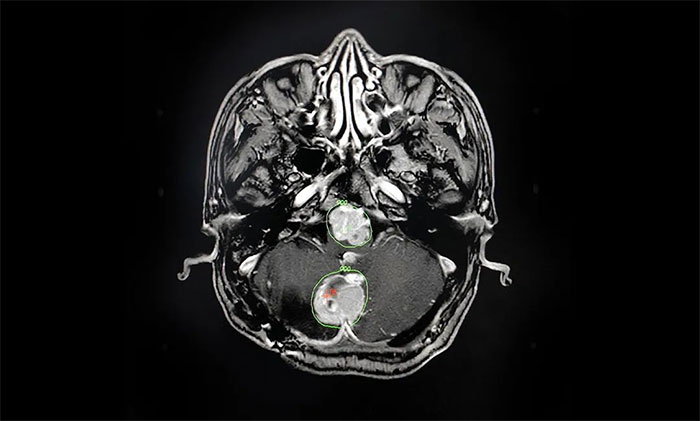

入院后,肿瘤科(放疗)头部伽玛刀组主任陈琦为他完善了MRI检查,明确多处肿瘤的位置、体积(单体肿瘤最大直径约2.7cm)。经与神经外科、医学影像科等开展MDT多学科联合会诊,评估复发肿瘤病灶毗邻脑干等重要功能区,手术难度高、风险大,可通过头部伽玛刀治疗,控制肿瘤生长,快速缓解临床症状。

▲ 科学制定伽玛刀治疗计划